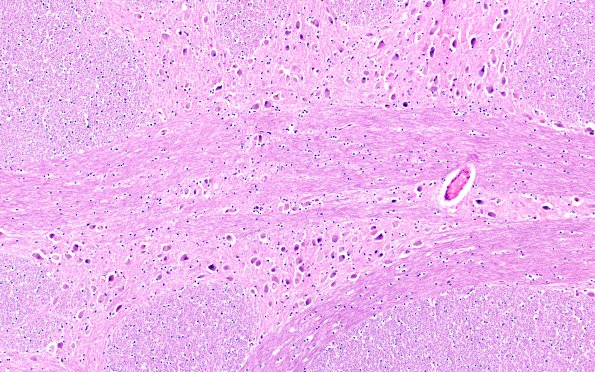

5E1 NCL (Case 5) Pons 10X A

5E1,2 Pontine neurons are similarly distended with lipopigment